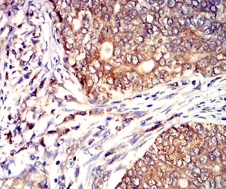

IHC    1/200 - 1/1000